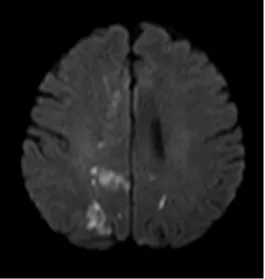

激素治疗后

治疗一段时间后,患者症状得到显著改善。复查“磁共振高分辨颅内血管壁成像”显示,脑内多处血管壁强化程度显著减低,右侧大脑前动脉血管壁强化程度明显减少,标志着治疗取得关键性成效。目前患者症状稳定,血管壁炎症反应得到有效控制,患者及家属对治疗效果给予高度认可。